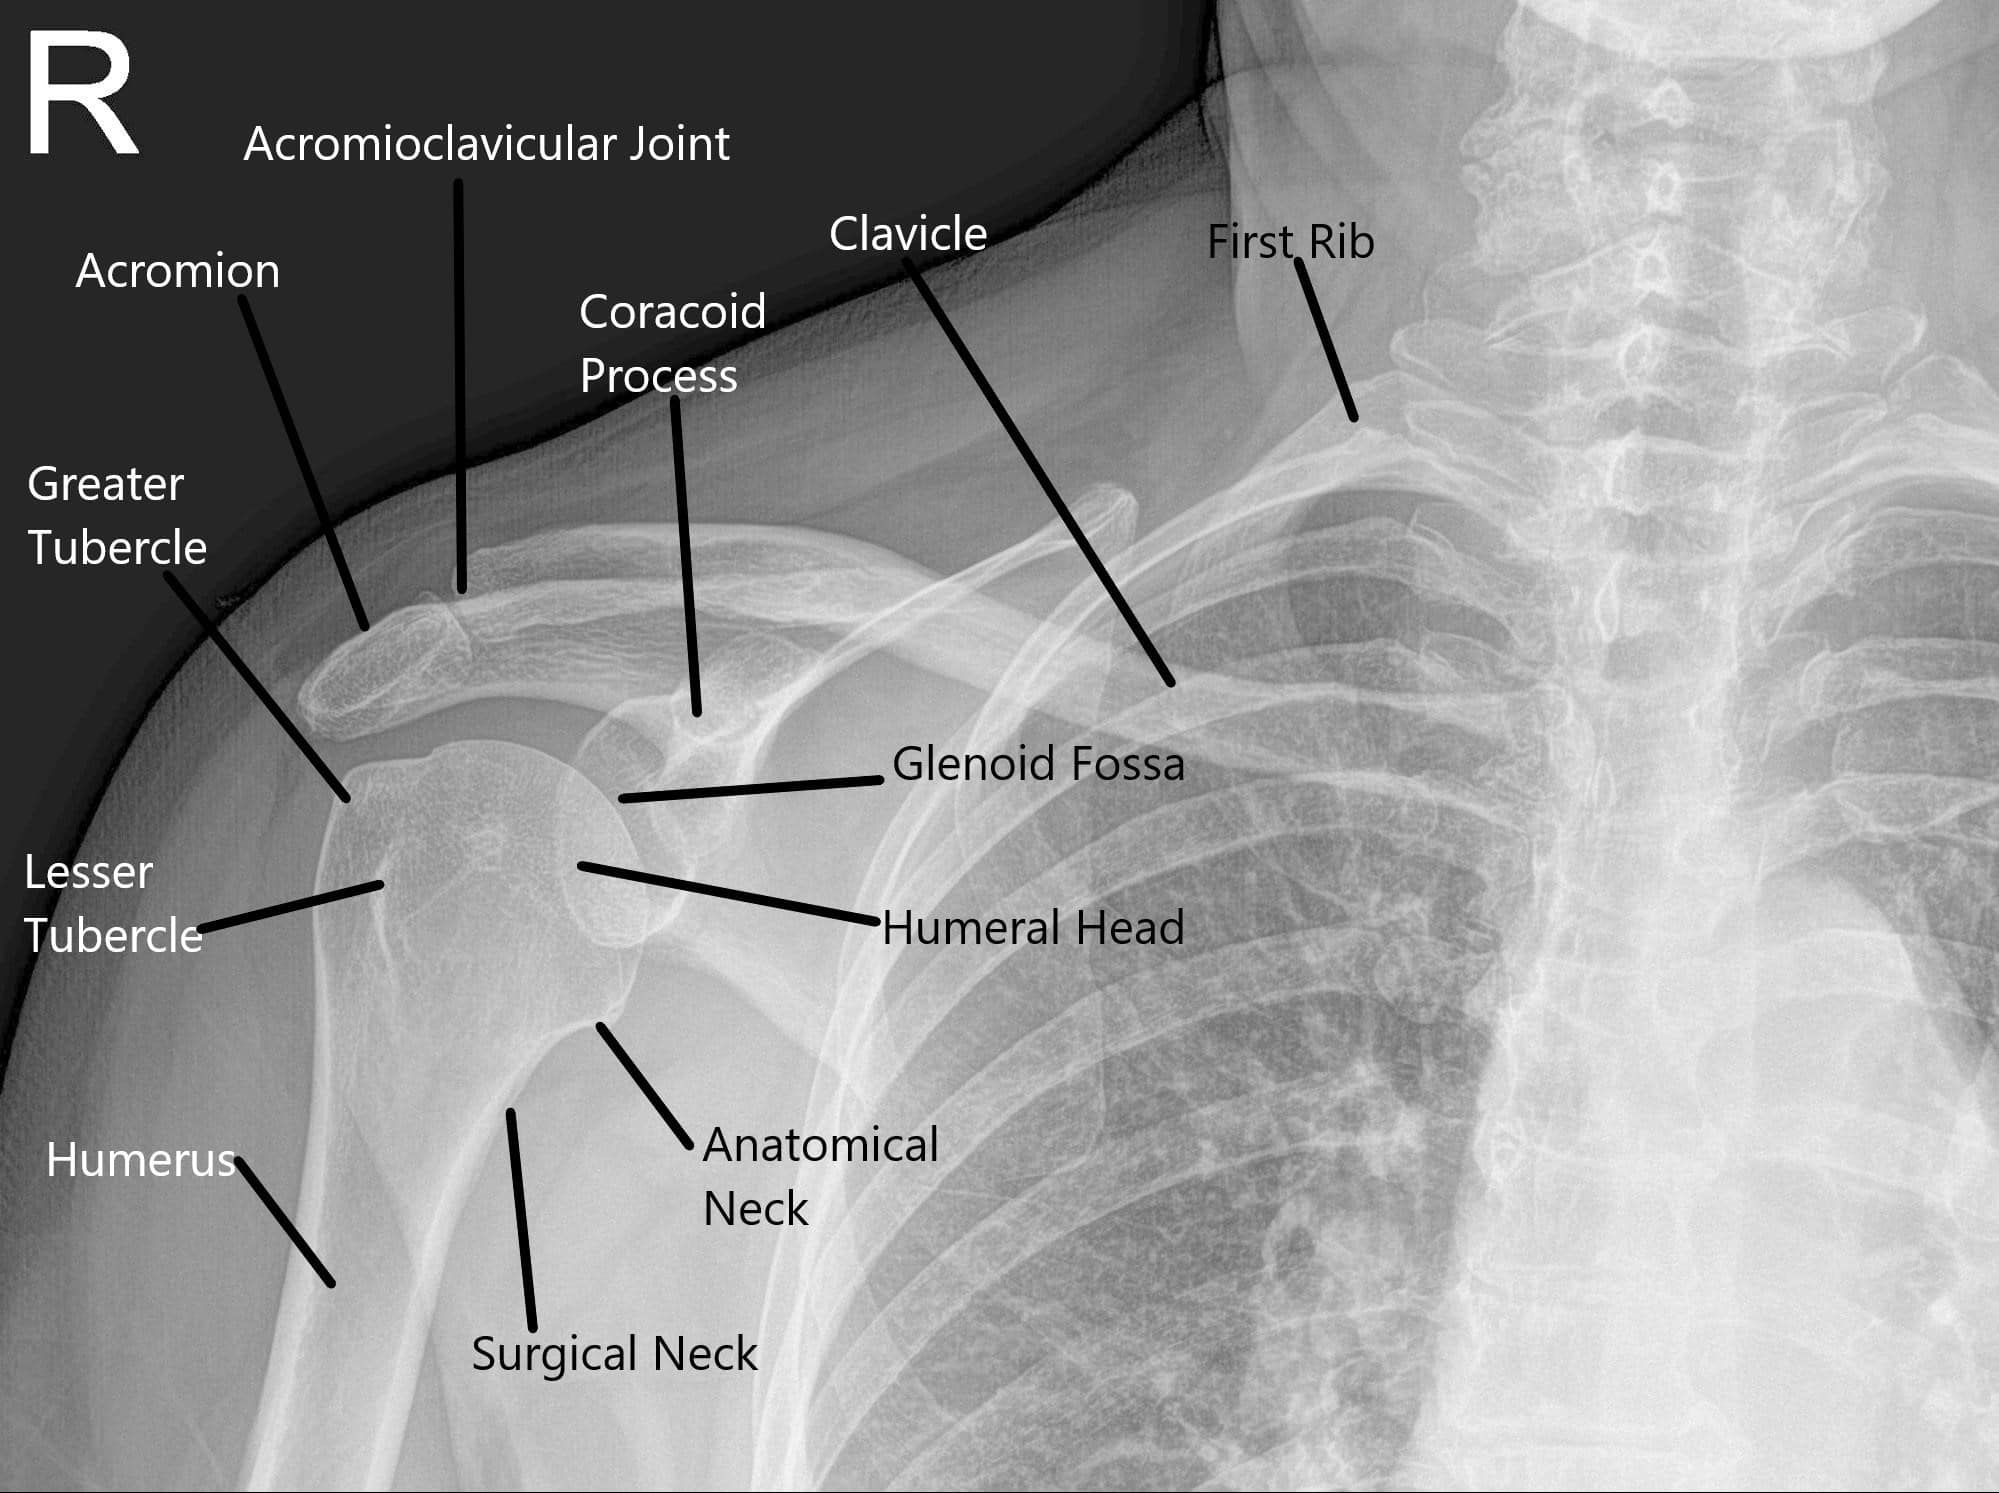

X-ray showing the normal shoulder anatomy.

How the Body Part Normally Works? (Relevant Anatomy)

The shoulder joint consists of the humerus (upper arm bone), scapula (shoulder blade), and clavicle (collarbone). The ball of the humerus fits into the shallow socket of the scapula, forming a ball-and-socket joint. This configuration provides a large range of motion. Ligaments, tendons (like the rotator cuff), and the labrum stabilize and support the joint, allowing for smooth movement and flexibility.